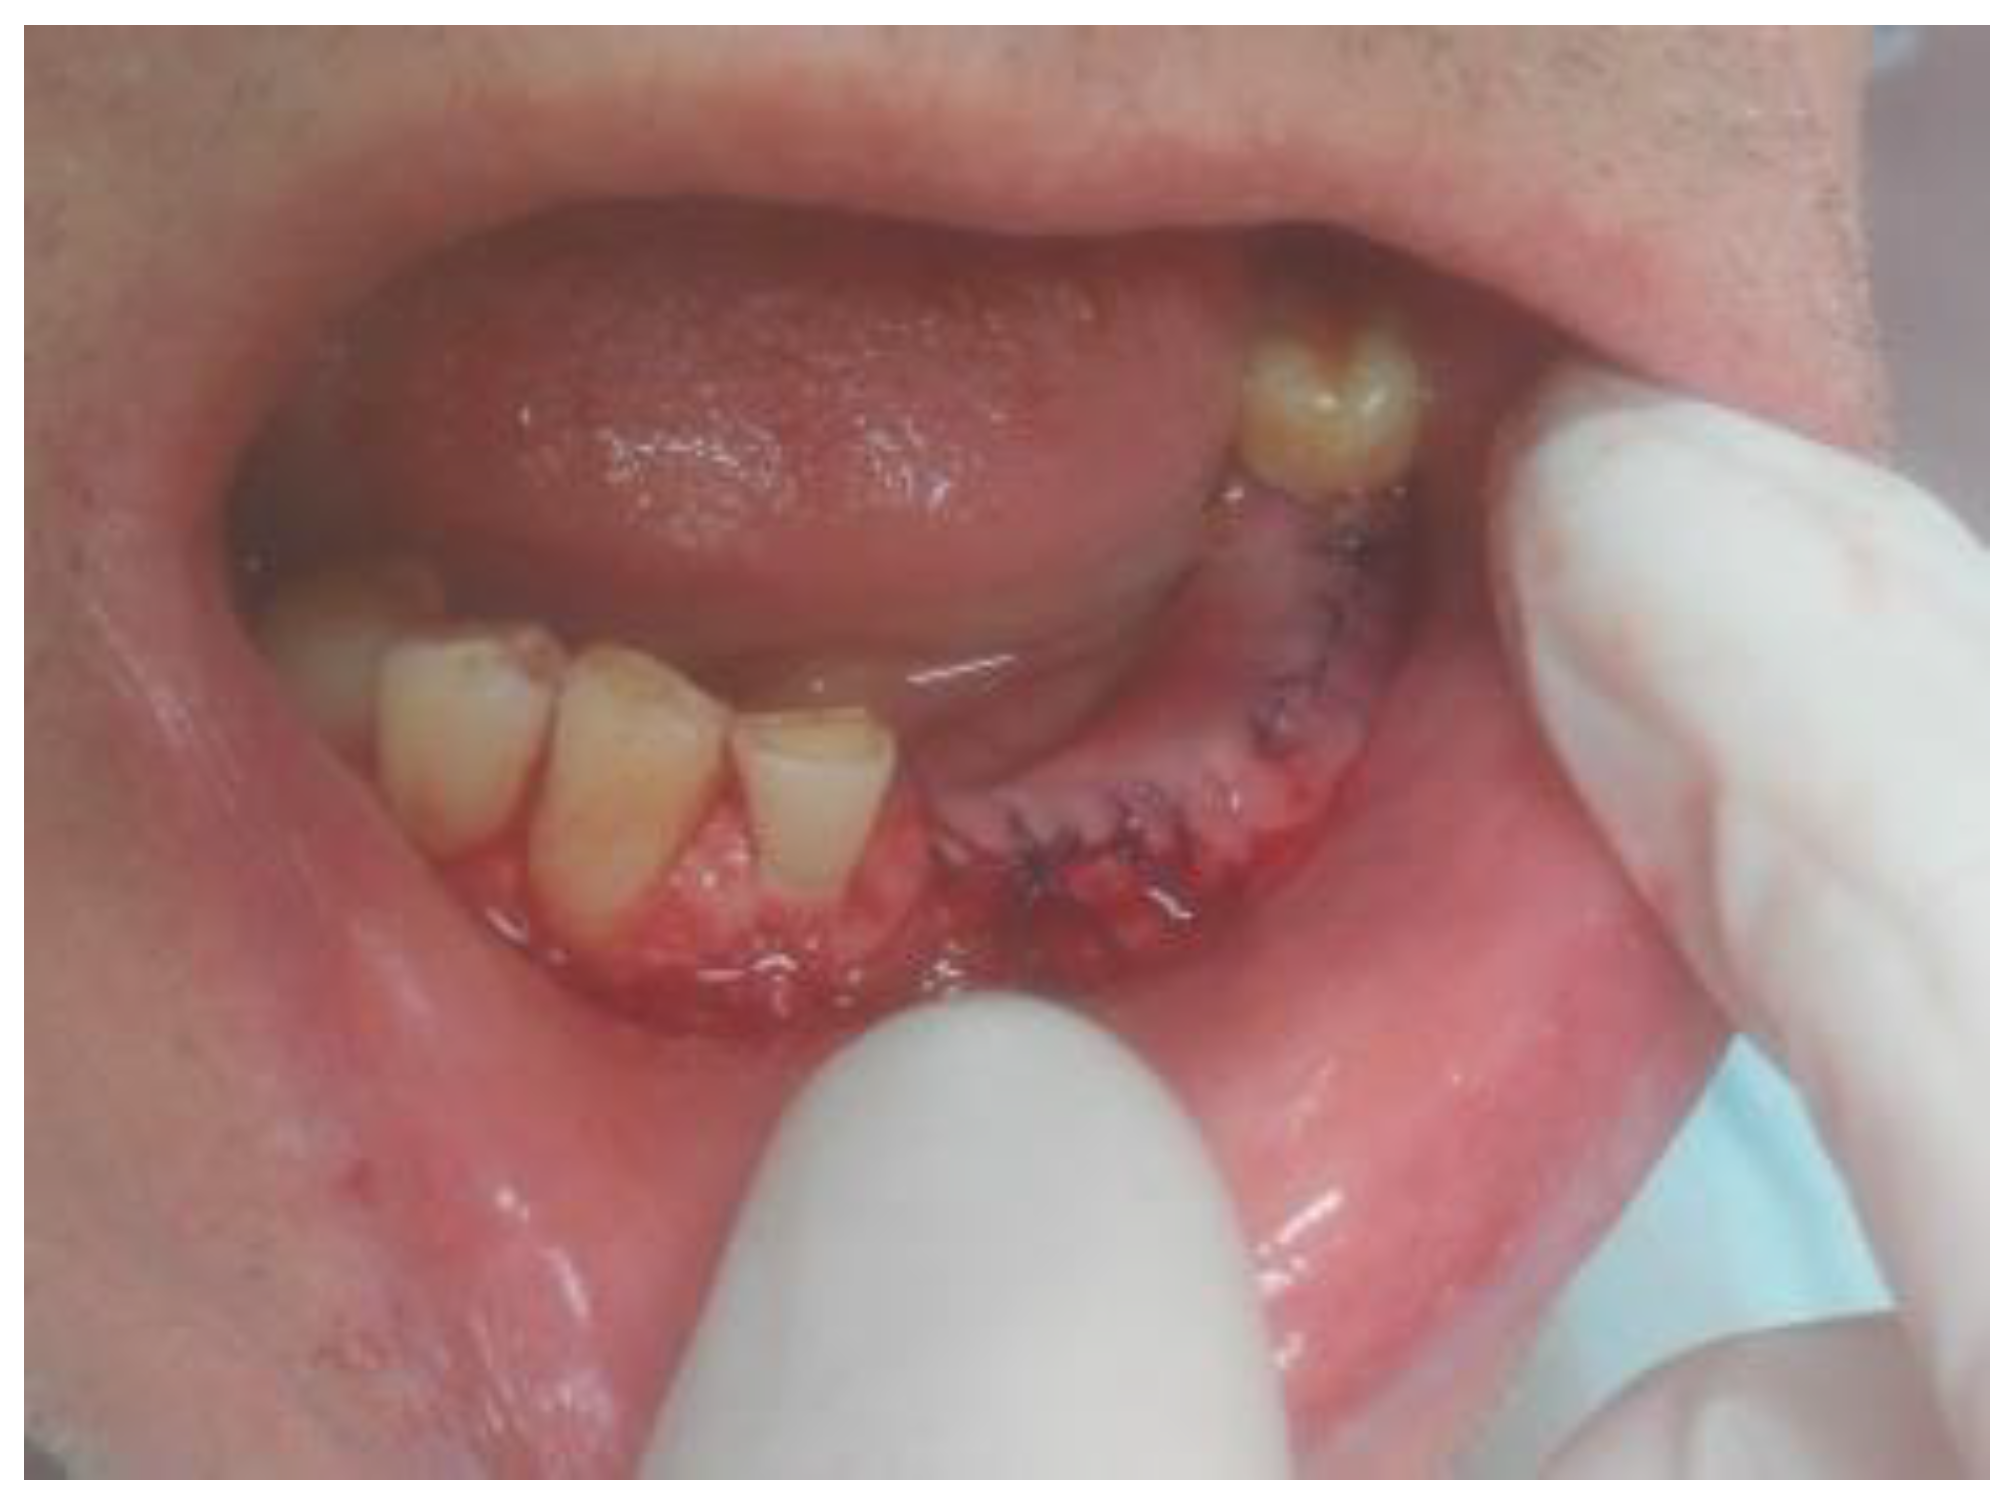

Because some clinical characteristics suggested the presence of either OKC or ameloblastoma, a small diagnostic biopsy was performed at the top of the alveolar ridge between teeth 34–35 in local anesthesia to evaluate the type of lesion microscopically. At first, the 0.1% CHX (chlorhexidine gluconate) (Eludril, Pierre-Fabre Oral care, France) solution was used in the oral cavity The surrounding area was scrubbed with alcohol–ethanol 96% solution-AHD 1000 solution (MediLab, Lysoform, Germany) and protective sterile vaseline (Unilever, England). Lignocaine with Norepinephrine 2% (ampule, 2 mL, Polfa-Warszawa, Poland) was used for local anaesthesia. A standard No 15c B surgical blade (Swann Morton, WR Swann, Owlerton Grn, Hillsborough, Sheffield, England) was used for the modified sulcular incision between two malpositioned teeth 33–34, extending towards the dental sulcus. After elevating the mucosal flap with an elevator, a sample of cystic-like tissue with keratin mass was taken for microscopic evaluation. The wound was sutured with 3-0 interrupted vertical mattress sutures (Dafilon, B Braun, Aesculap AG Am Aesculap-Platz, Tuttlingen Germany). Histopathologic (HP) evaluating indicated OKC.

Figure 2. Intraoral photograph visualizing labial cortical swelling with crepitation and soft tissue elevation.